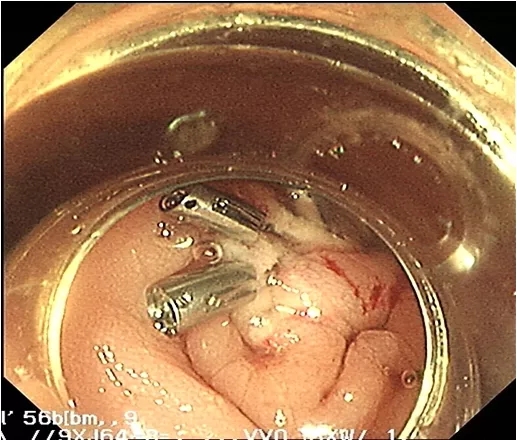

经小瑞家属签字同意后,经过周密的检查前准备,消化内科黄理副主任医师及陈丽芬副主任医师带领内镜中心医护团队,联合麻醉科,共同为患儿实施全麻下无痛胃肠镜检查。术中,镜下可见横结肠距肛门55cm处见一大小约4.0cmX4.0cm的息肉,几乎堵住整个肠腔。原来小瑞的这些症状竟是结肠巨大息肉在“作祟”,在征得家长的同意后,黄理副主任医师及陈丽芬副主任医师凭着丰富的经验、娴熟的手术操作,将整块息肉完整切除。同时,麻醉师也在为小儿实施精准麻醉,确保术中患儿稳定,全程30分钟,手术非常顺利。术后五天患儿痊愈出院,病理结果提示:(横结肠)幼年性息肉。

肠镜下可见图像